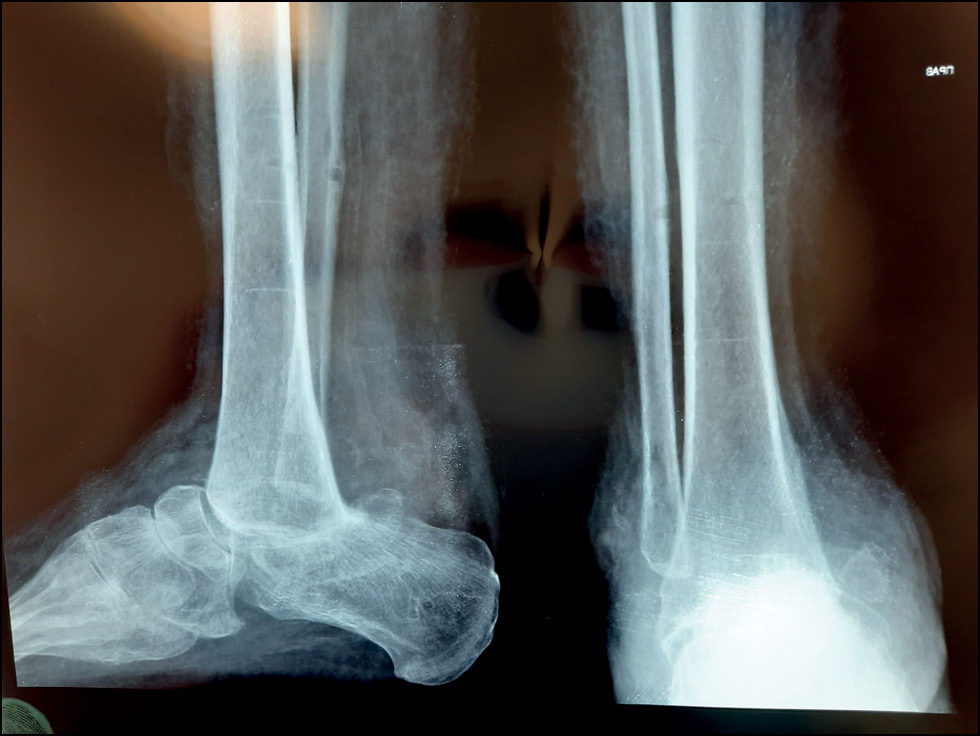

При рентгенологическом обследовании выявлен лизис таранной кости правой стопы на 2/3 от своего объёма (преимущественно тела таранной кости) со слабо выраженными признаками снижения МПКТ: истончение кортикальной пластинки, крупноячеистая трабекулярная микроструктура, усиленная рентгенопрозрачность (рис. 2, 3).

Рис. 2. Рентгенограмма в передне-задней проекции до лечения.

Fig. 2. X-ray image in anterior-posterior projection before treatment.

Рис. 3. Рентгенограмма в боковой проекции до лечения.

Fig. 3. X-ray image before treatment in lateral projection.